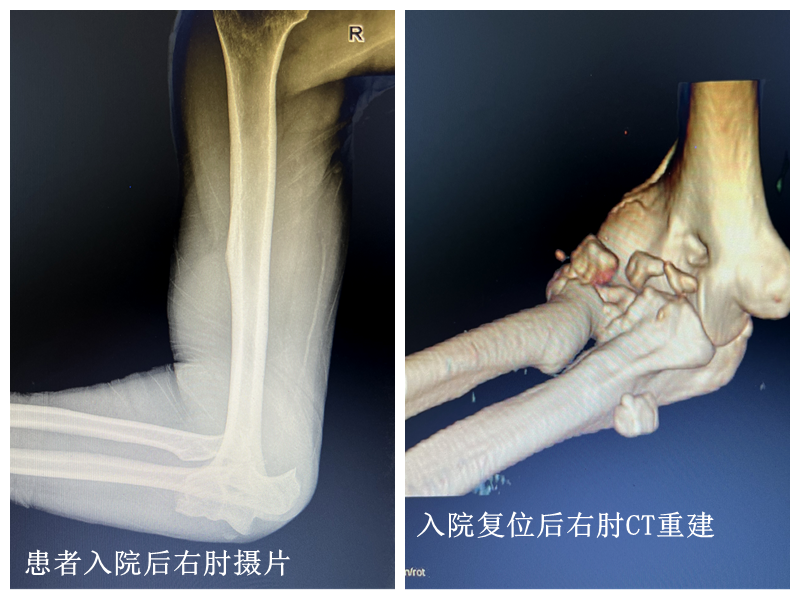

该患者为76岁男性,右肘关节脱位伴外侧副韧带撕脱伤、右桡骨小头粉碎性骨折、右冠状突粉碎性骨折(俗称肘关节恐怖三联征)。为提高术中操作的精准程度,减少不必要的手术创伤,术前,骨一科主任高学良副主任医师根据患者CT扫描数据,利用人工智能3D打印技术1:1完整复刻患者骨折部位的模型。骨一科团队充分进行术前讨论,根据3D打印模型,反复模拟手术操作,精准规划手术路径方案,成功实施右冠状突粉碎性骨折复位固定+右桡骨小头粉碎性骨折复位固定+外侧副韧带修复重建术。